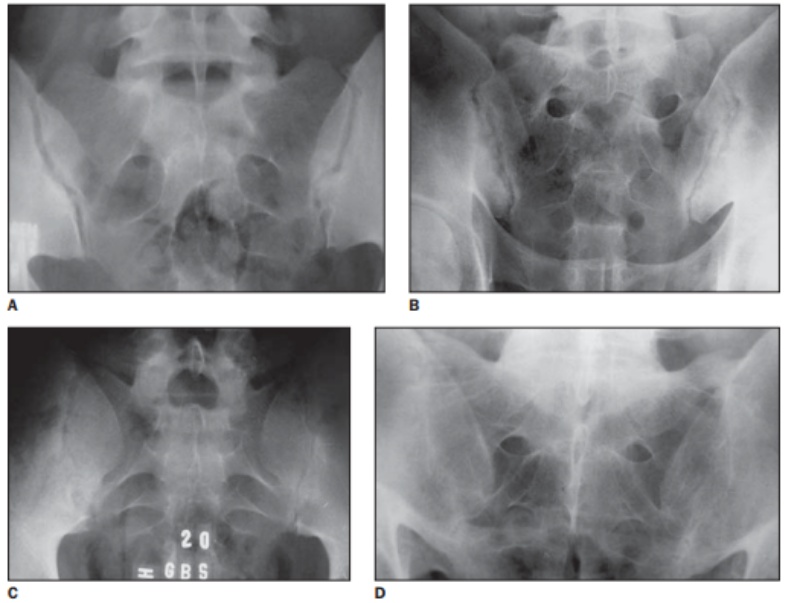

Viêm khớp cùng chậu thường trãi qua 4 giai đoạn, mỗi giai đoạn sẽ có những biểu hiện khác nhau trên phim chụp X quang. (2)

Hình ảnh Xquang viêm khớp cùng chậu

• Hình A – Mức độ 0 – Bình thường.

• Hình B – Mức độ 1 – Nghi ngờ: Có sự xuất hiện xơ cứng bề mặt khớp nhưng khoảng cách khớp vẫn bảo tồn.

• Hình C – Mức độ 2 – Tiến triển: Quan sát thấy có sự đặc xương ở bờ khớp, dính một phần khớp cùng chậu.

• Hình D – Mức độ 3 – Nặng: Dính khớp cùng chậu hoàn toàn.